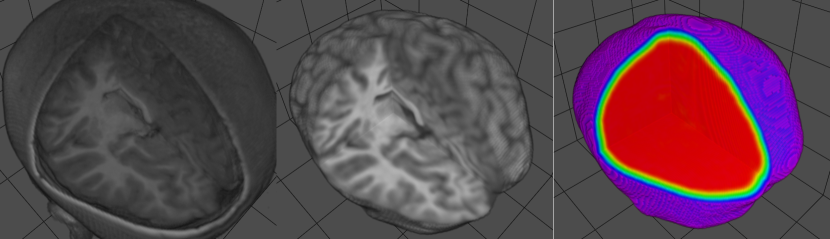

Recently, mask-guided attention has demonstrated improved performance for different purposed such as image classification (Wang et al., 2021), image re-identification (Cai et al., 2019), image recover occluded pedestrian detection (Pang et al., 2019). However, to the best of our knowledge, there are few studies on developing mask-guided attention in image reconstruction, specifically for brain image preprocessing. In this study, we developed a novel mask-guided attention module that utilizes brain maks to preprocess and reconstruct meaningful MRI and 3D neonatal ultrasound images. Morover, sinusoidal positional encoding is used to enhance the models ability to process distinct modalities within the same framework. MGA-Net is engineered to perform critical tasks, such as brain extraction, bias field correction, and noise removal for MRI, as well as similar preprocessing steps and total brain volume estimation for 3D neonatal US images. This integrated approach not only addresses the limitations of data scarcity but also enhances the model’s applicability and effectiveness in clinical settings. The validation of MGA-Net was rigorously performed using diverse MRI datasets, including those collected under less standardized conditions, thus demonstrating the model’s robustness across varying data quality (Figure 1. Additionally, a dataset comprising real 3D ultrasound images from preterm neonates was used to further validate and refine the ultrasound preprocessing capabilities of MGA-Net. This approach not only enhances the utility of the available data and maximizes the efficacy of preprocessing tasks across modalities.

Refer to caption

Figure 1: Example of brain extraction and preprocessing of T1w MRI images using MGA-Net across various postmenstrual ages, ranging from neonatal (25 weeks to 50 weeks) to eight years old patients.